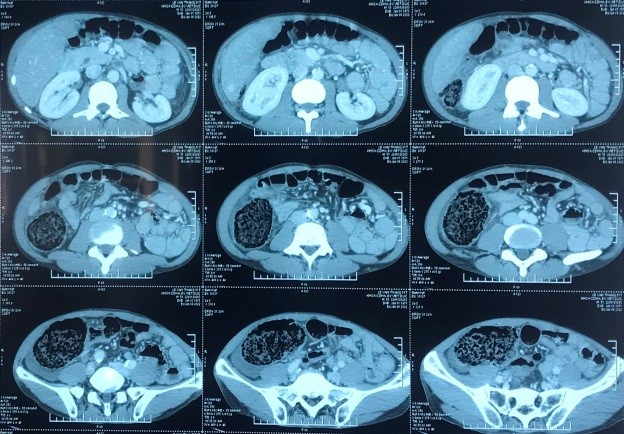

| Hình chụp X-quang của bệnh nhân. Ảnh: Bệnh viện Hữu nghị Việt Đức. |